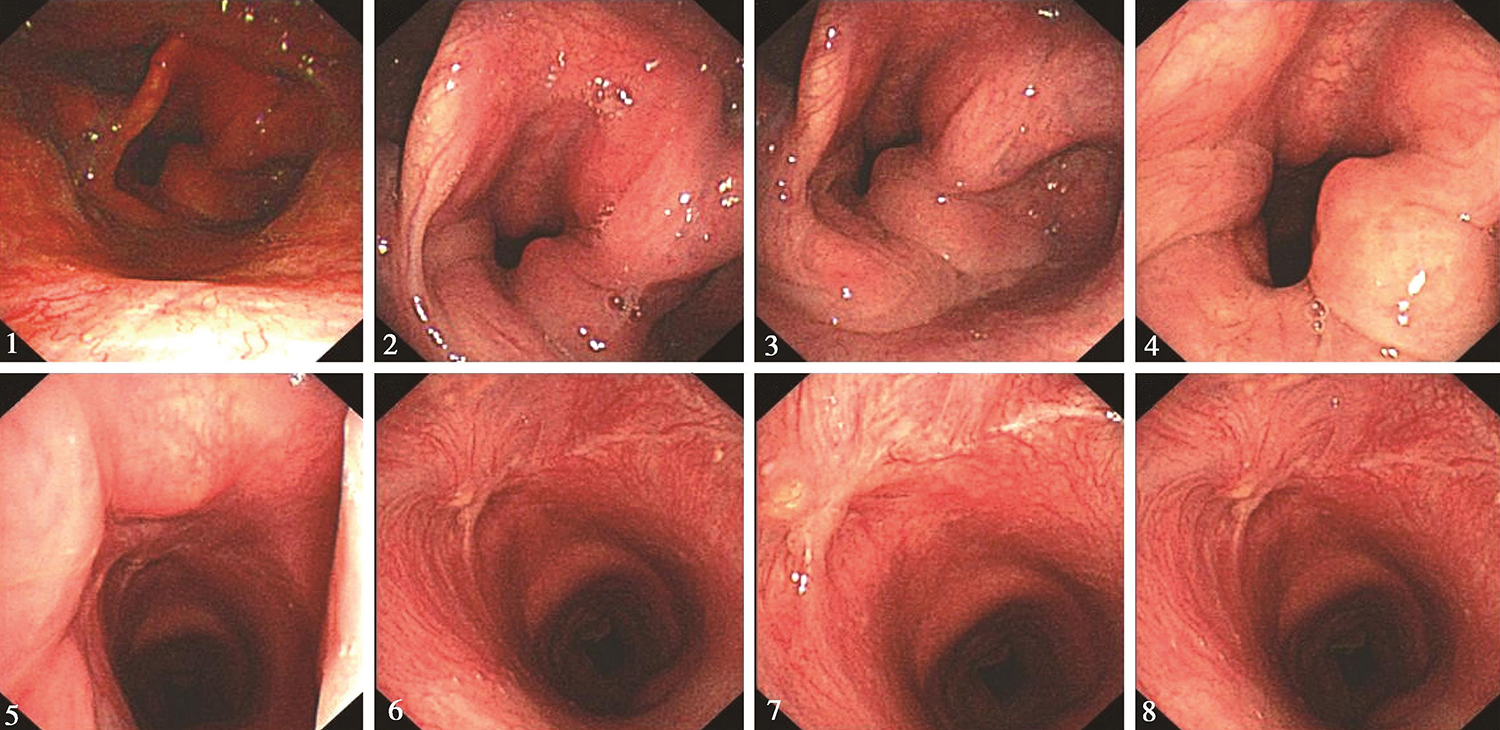

内镜所见:鼻腔进镜顺利。鼻咽部结构完整,黏膜光滑,未见明显异常。口咽双侧扁桃体未见肿大。舌根部基本平整。下咽部表面基本平整,未见明显异常。喉部会厌及双侧披裂结构完整。声门区右侧声带表面略欠光滑,覆盖白斑,侵及全长,向前累及前联合,左侧声带前端显露不佳,警惕受累及。右侧室带黏膜充血,考虑受侵犯。双侧声带活动正常。声门下未见侵及(图1)。

内镜诊断:声门型喉癌,已有病理诊断,病变较浅表,符合原位癌。

图1 喉镜示声门区右侧声带表面覆盖白斑

内镜所见:“喉癌术后2个月”,鼻腔进镜顺利。鼻咽部结构完整,黏膜光滑,未见明显异常。口咽双侧扁桃体未见肿大。舌根部基本平整。下咽部表面基本平整,未见明显异常。喉部呈术后改变,会厌及双侧披裂保留,双侧声带切除,术区表面基本平整,局部可见瘢痕样表现(图5)。双侧披裂略显水肿,声门裂闭合不全。

内镜诊断:喉癌术后2个月,术区表面平整,未见复发征象。

图5 2017年6月9日复查喉镜